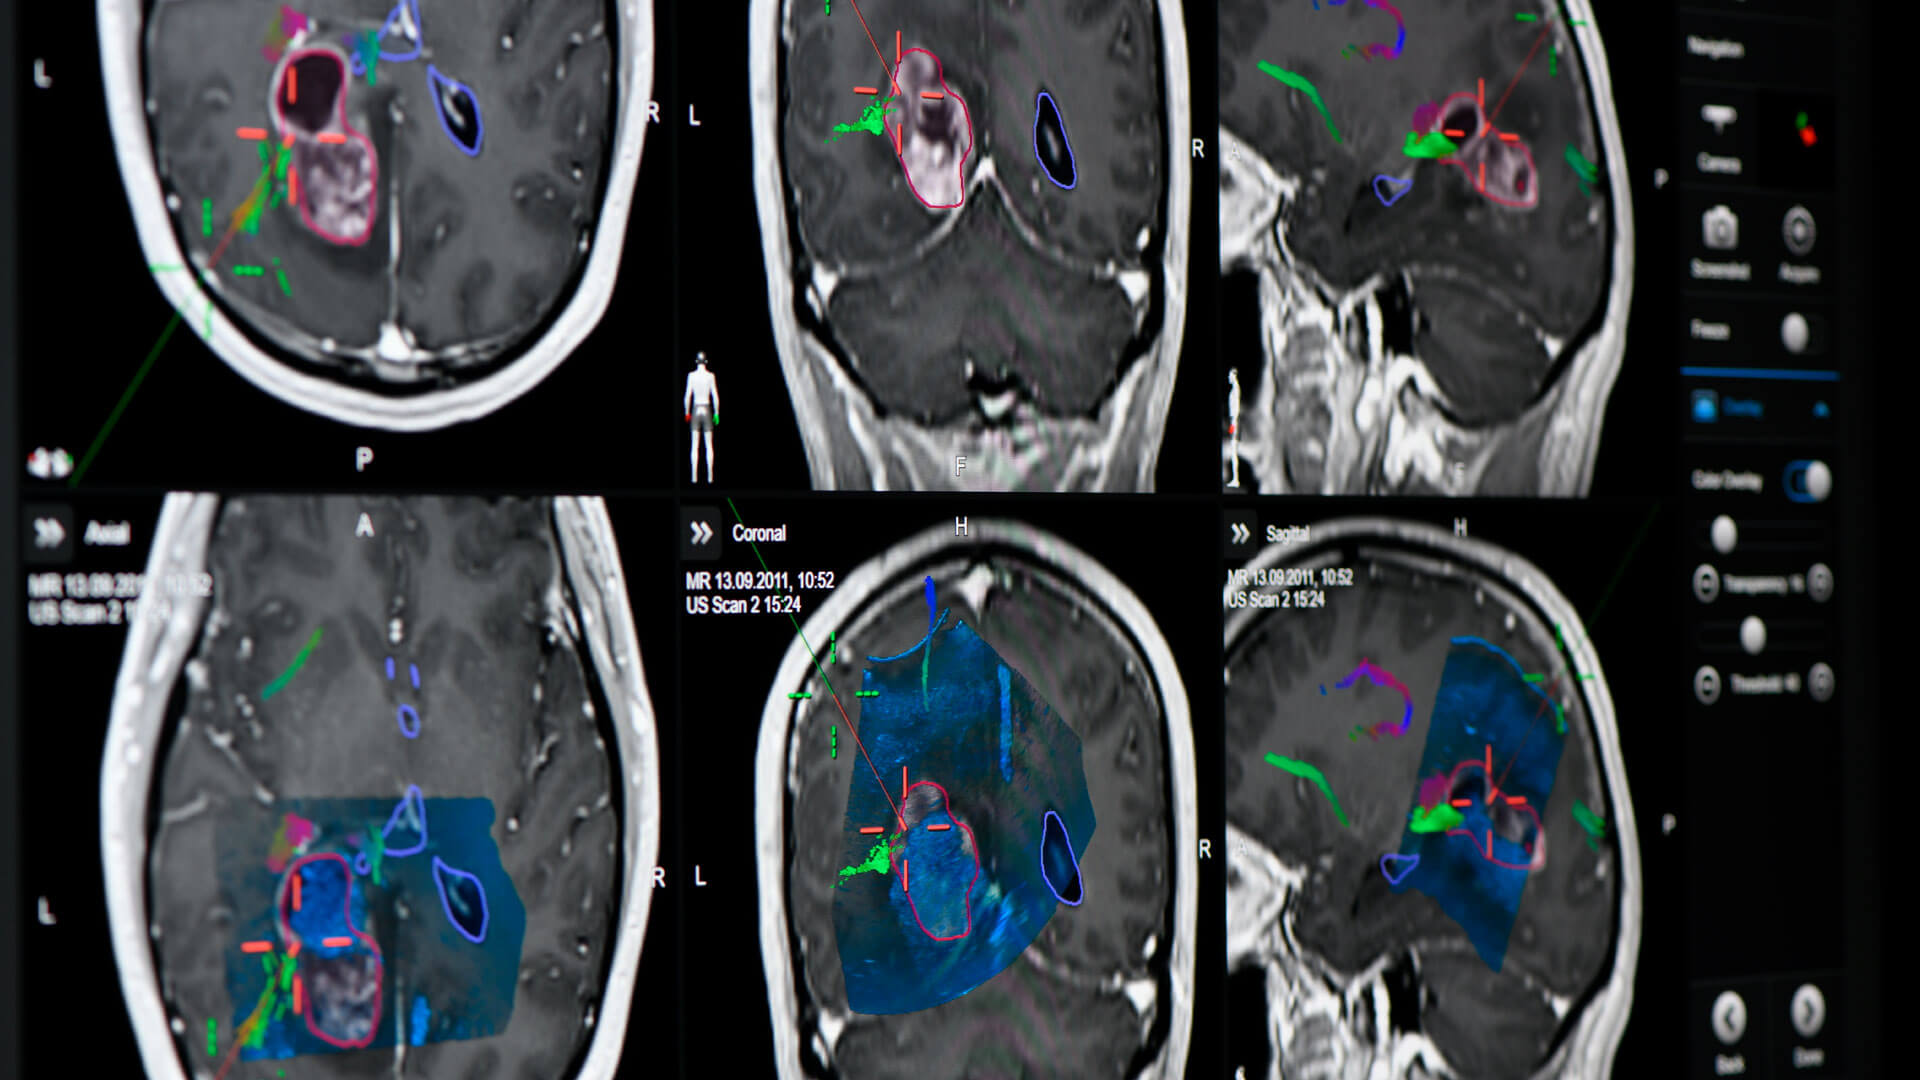

Brainlab neuronavigation combines ease of use with extended functionality tailored to surgeons’ needs